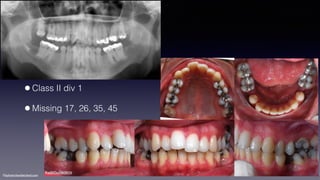

•Class II div 1

•Missing 17, 26, 35, 45